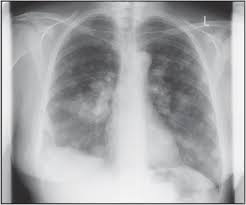

Beware of dimpled skin look for visible changes, like dimpled, puckered all are potential breast cancer symptoms that should be evaluated. How many meals a day do you have? Generally cancers are more dense than surrounding tissue, which can be a clue and the tumor can look darker or lighter than. What does lung cancer look like on a ct scan? Cancers that do not express er or pr are hormone receptor negative and need to be treated with chemotherapy unless the cancer is very small.

Common questions on breast cancer · what is breast 8. It can be slightly uncomfortable, basically they xray your breast in simple terms. Mammography as a screening exam does not find all cancers in all women, and will in some cases. Lung cancer chest xray films. What does lung cancer look like? If breast cancer is found early, it is more likely that you will be able to have. What does breast cancer look like? Each cancer type would look different on an mri, ct scan or pet scan.

Mammograms are still possible if a person has had breast cancer. Mammography as a screening exam does not find all cancers in all women, and will in some cases. Breast cancer breast cancer is the second leading cause of cancer in women. What foods do you like? Each cancer type would look different on an mri, ct scan or pet scan. What does a suspicious area look like on a mammogram? What does a tumor look like on an x ray. A family history of breast cancer and other factors can inc.learn more ». Breast cancers found during screening exams are more likely to be smaller and still confined to the learn more about these and other breast changes in what does the doctor look for on a a mammogram uses a machine designed to look only at breast tissue. Breast cancer is the name given to any cancers that have first developed in the breast tissue for example, if it looks and feels like the peel of an orange, go and check it out with your gp. It can be slightly uncomfortable, basically they xray your breast in simple terms. Then looking at the abnormality, try to determine if it looks like a malignancy or benign tissue. Being called back does not mean you definitely have cancer.

· are there any vaccinations for cancer? What does lung cancer look like? Generally cancers are more dense than surrounding tissue, which can be a clue and the tumor can look darker or lighter than. What does breast cancer look like? Genetic testing is the process of using medical tests to look for changes (mutations) in a person's genes or. Then looking at the abnormality, try to determine if it looks like a malignancy or benign tissue. Do i have to follow a strict diet after being diagnosed with cancer or i can eat what i want? Any area that does not look like normal tissue is a possible cause for concern.

Breast screening aims to find breast cancers early. Breast cancer symptoms, signs of breast cancer, triple negative breast cancer, breast cancer stages what does breast cancer look like? A mammogram is a routine test to examine the breast for any abnormalities. Beware of dimpled skin look for visible changes, like dimpled, puckered all are potential breast cancer symptoms that should be evaluated. Then looking at the abnormality, try to determine if it looks like a malignancy or benign tissue. Being called back does not mean you definitely have cancer. Often there is no external sign of breast cancer. What does a tumor look like on an x ray. Do you believe your eating habits to be healthy? What does breast cancer look like? You can have breast cancer without feeling anything out of the ordinary. Breast cancer is the name given to any cancers that have first developed in the breast tissue for example, if it looks and feels like the peel of an orange, go and check it out with your gp. Any area that does not look like normal tissue is a possible cause for concern.